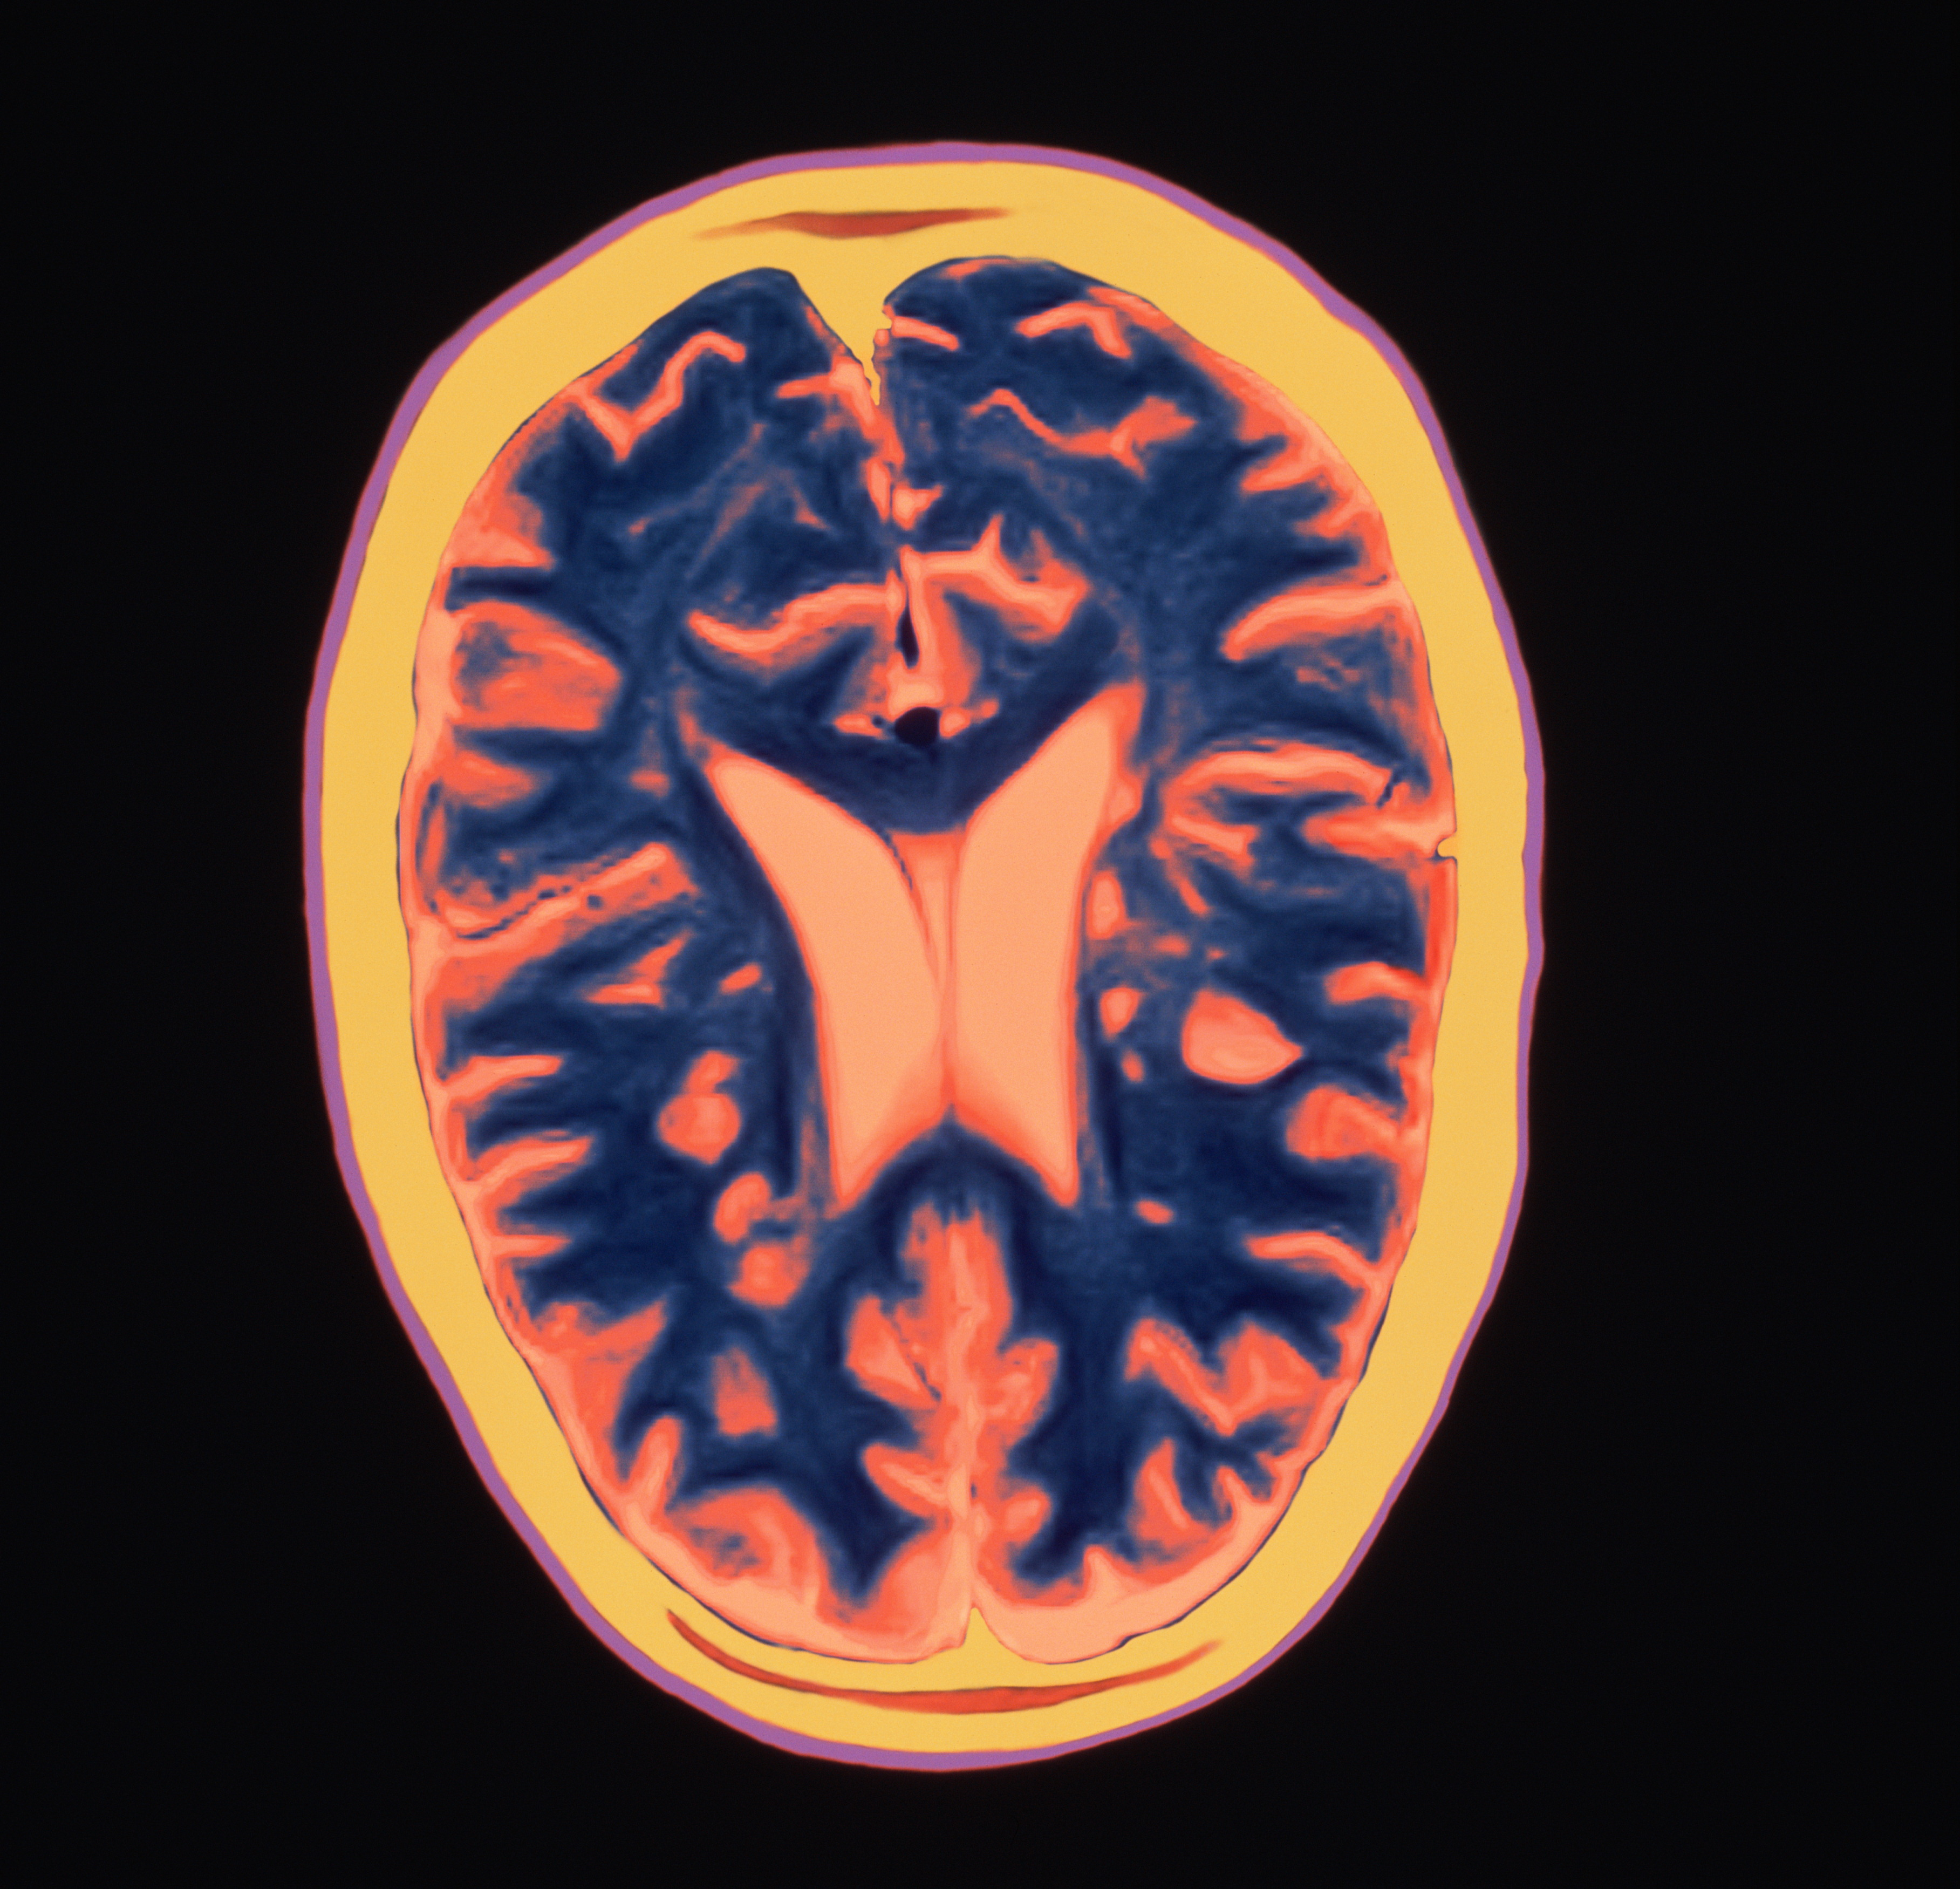

Approximately 400,000 people in the U.S. and more than 2 million worldwide suffer from MS, a chronic disease for which there is no cure. MS is characterized by abnormal attacks by the immune system on myelin sheaths of nerve cells in the brain, optic nerves, and spinal cord. The myelin sheath supports and insulates the nerve cells. When it is attacked, it becomes inflamed and eventually sustains damage. Symptoms of damage to the myelin sheath include fatigue, pain, muscle weakness, and difficulty seeing, which can eventually lead to disability, including the inability to walk.